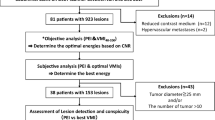

The study was approved by our institutional review board. Seventy-six retrospectively selected patients with known primary cancer likely to metastasize to the liver underwent MDCT from June 2004 to September 2007 at RWTH Aachen University Hospital in the Department of Diagnostic Radiology to detect possible malignant hepatic metastases or for follow-up of known liver metastases. Corresponding to the contrast media enhancement of the hepatic lesions, patients were divided into three groups with hyperdense (n = 35), hypodense (n = 20) and heterogeneous (n = 21) liver metastasis (Table 1).

In 76 patients, 165 target lesions were found and evaluated first by the radiologist and afterwards with the software tool. All 165 lesions were correctly segmented with the software tool.